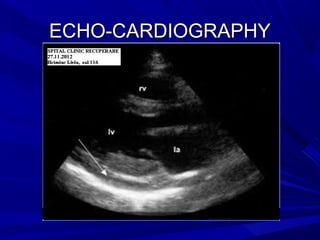

CARDIAC TAMPONADECARDIAC TAMPONADE

ECHO-CARDIOGRAPHYECHO-CARDIOGRAPHY

Signs of high fluid quantitySigns of high fluid quantity

Signs of high pericardial pressureSigns of high pericardial pressure

Signs of high systemic venous pressureSigns of high systemic venous pressure

Excludes other pathologies:Excludes other pathologies:

RV myocardial infarctionRV myocardial infarction

Pulmonary embolismPulmonary embolism

MyocarditisMyocarditis

Swinging heartSwinging heart

RA diastolic collapseRA diastolic collapse

RV diastolic collapseRV diastolic collapse

LA, LV diastolic collapseLA, LV diastolic collapse

IVC distensionIVC distension

< 50% collapse in inspiration< 50% collapse in inspiration